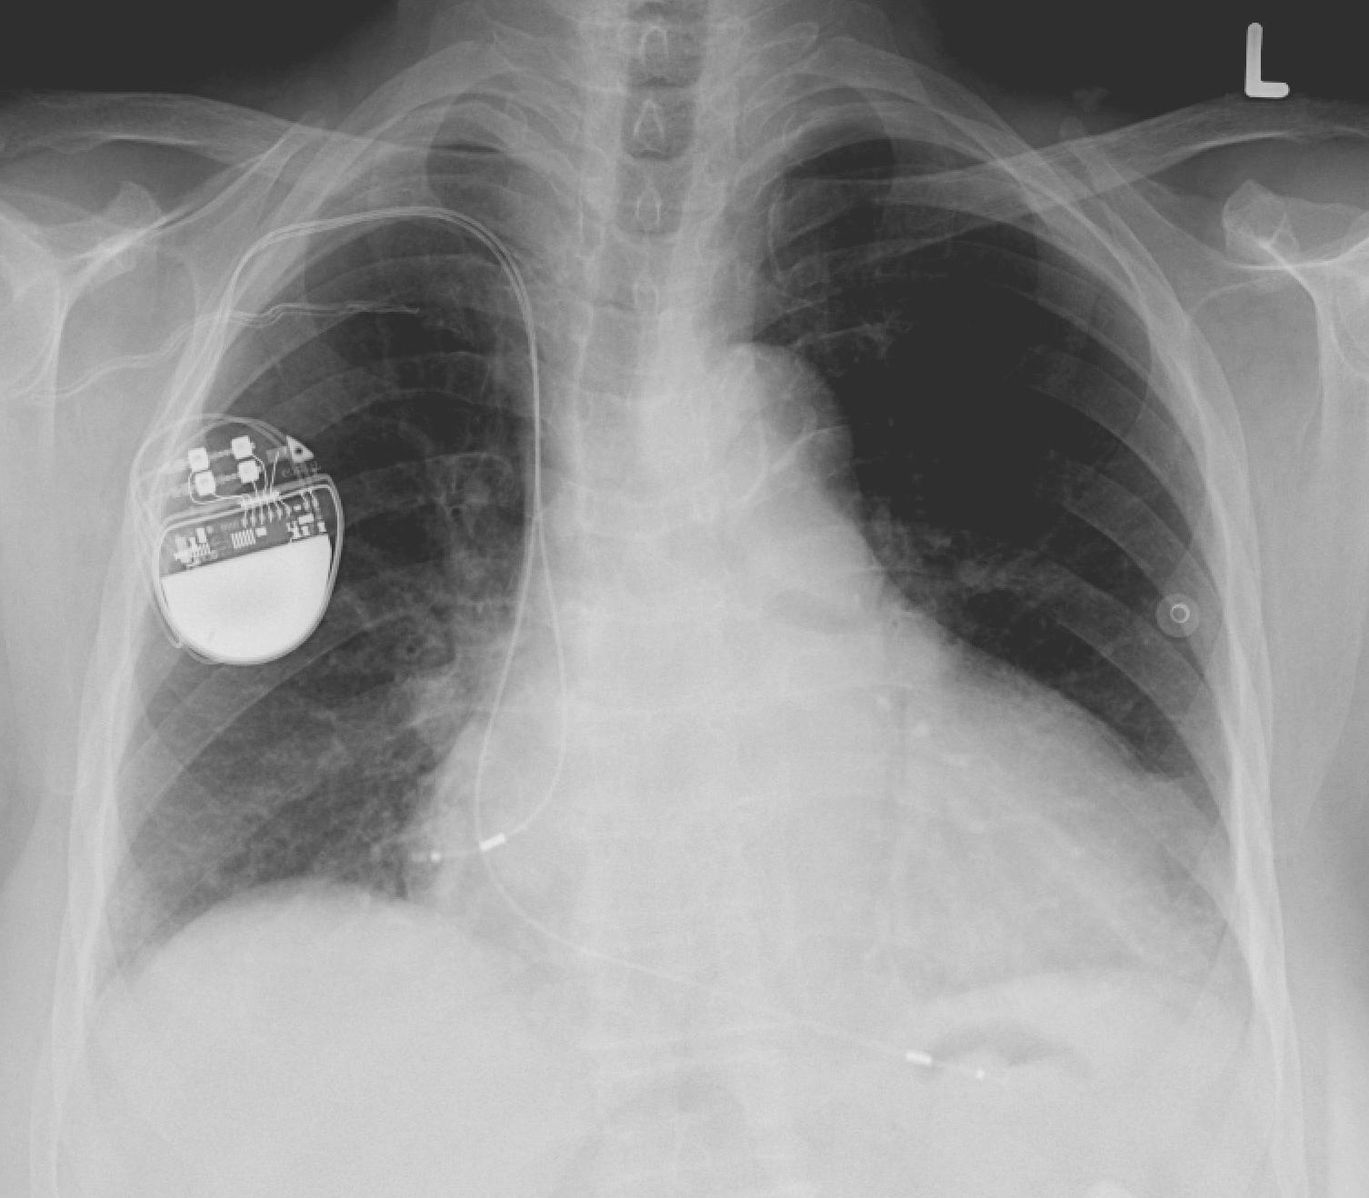

1369px-Pacemaker.jpg

资料图

其中83%为男性,并且他们所有人都植入了电子设备(CIEDs),换言之,他们都曾通过手术在体内安装了起搏器和除颤器。